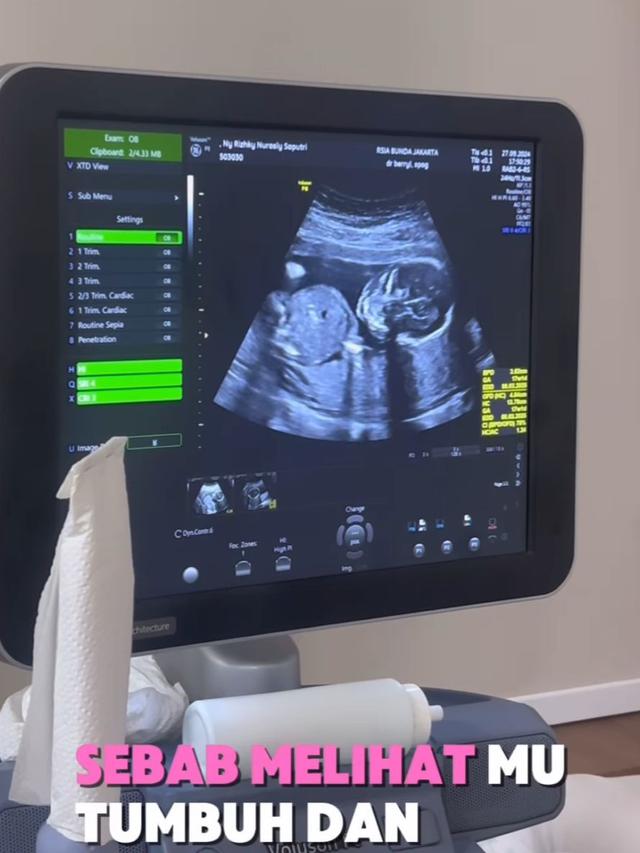

Melalui sebuah video yang dibagikan di Instagram reels, Kiky mengungkapkan bahwa ia tengah mengandung lagi. Setiap detik dalam video tersebut dipenuhi dengan rasa syukur dan harapan besar yang terpancar dari wajah Kiky.

Setelah melewati masa-masa yang menantang, Kiky Saputri mengumumkan kabar gembira pada 29 Juni 2024, bahwa ia mendapatkan anugerah dari Tuhan untuk mengandung lagi.

Dalam video yang dibagikan di Instagram, Kiky tampak sangat emosional saat menyampaikan berita tentang kehamilan keduanya, dengan disertai doa dan harapan agar proses kehamilan ini berlangsung dengan baik hingga persalinan. Kiky terus-menerus mengungkapkan rasa syukur atas kesempatan kedua ini dan berharap dapat menjaga serta merawat calon bayinya hingga mereka dapat bertemu di dunia ini.

Pada 4 Oktober 2024, Kiky secara resmi memberitahukan kehamilannya melalui Instagram. Dalam postingannya, Kiky menulis, "Bismillah... Alhamdulillah... Terima kasih untuk semua doa yang baik. Kami juga berharap, semoga yang belum... segera diberi kesempatan."

Dengan perut yang sudah terlihat membesar, Kiky berharap kehamilannya berjalan lancar hingga ia dan suaminya bisa bertemu dengan anak yang dinantikan. Pengumuman ini mendapat banyak komentar positif dan doa dari para penggemarnya, yang juga mendoakan kesehatan Kiky dan calon bayinya.